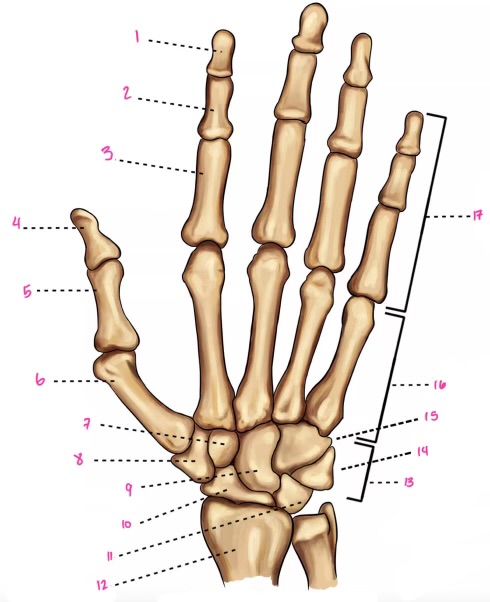

1

1

Hamate

2

New cards

2

Capitate

3

New cards

3

pisiform

4

New cards

9

Trapezoid

5

New cards

10

Trapezium

6

New cards

11

Scaphoid

7

New cards

14

Lunate

8

New cards

15

Triquetrum

9

New cards

16

Pisiform

10

New cards

17

Capitate

11

New cards

18

Hamate

1

Distal interphalangeal

13

New cards

2

Proximal Interphalangeal

14

New cards

3

Metacarpophalangeal

15

New cards

4

Intercapals

16

New cards

5

Distal radioulnar

17

New cards

6

Radiocarpal

18

New cards

7

Carpometacarpals

19

New cards

8

Metacarpophalangeal

20

New cards

9

Interphalangeal

7

Trapezoid

22

New cards

8

Trapzium

23

New cards

9

Capitate

24

New cards

10

Scaphoid

25

New cards

11

Lunate

26

New cards

13

Carpus

27

New cards

14

Triquetrul

28

New cards

15

Hamate

29

New cards

16

Metacarpus

30

New cards

17

Phalanxes